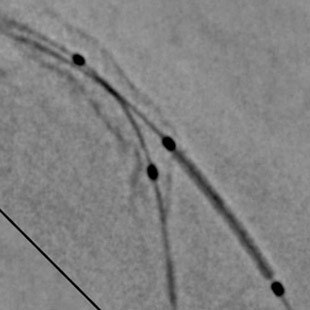

1. La solution PCI ASSIST comprend StentViz et StentVesselViz, qui sont des fonctions des systèmes de radiographie interventionnelle Innova IGS 5, Innova IGS 6, Discovery IGS 7 et Discovery IGS 7 OR.

3. Amélioration par rapport au même test sans l'option PCI ASSIST. L'amélioration de la visibilité et de la QI est mesurée sur Innova IGS 530 grâce à des fantômes utilisant différentes épaisseurs de plexiglas, des paramètres d'acquisition et la roue à rayons NEMA (réf 1), qui calcule le rapport du contraste des câbles mobiles et du niveau de bruit de fond. Le niveau d'amélioration de la qualité d'image lié à PCI ASSIST dépend des paramètres d'acquisitions, de la procédure clinique réalisée, de la taille du patient, des mouvements de l'image, de l'emplacement de la structure anatomique et des méthodes employées par l'établissement. Réf 1 : A new tool for benchmarking cardiovascular fluoroscopes; S. Balter, Radiation Protection Dosimetry, Vol. 94, No. 1-2 pp. 161-166 (2001). Applicable aux systèmes Innova IGS 5 (configurations IGS 520, IGS 530), Innova IGS 6 et Discovery IGS 7 (configuration IGS 730).